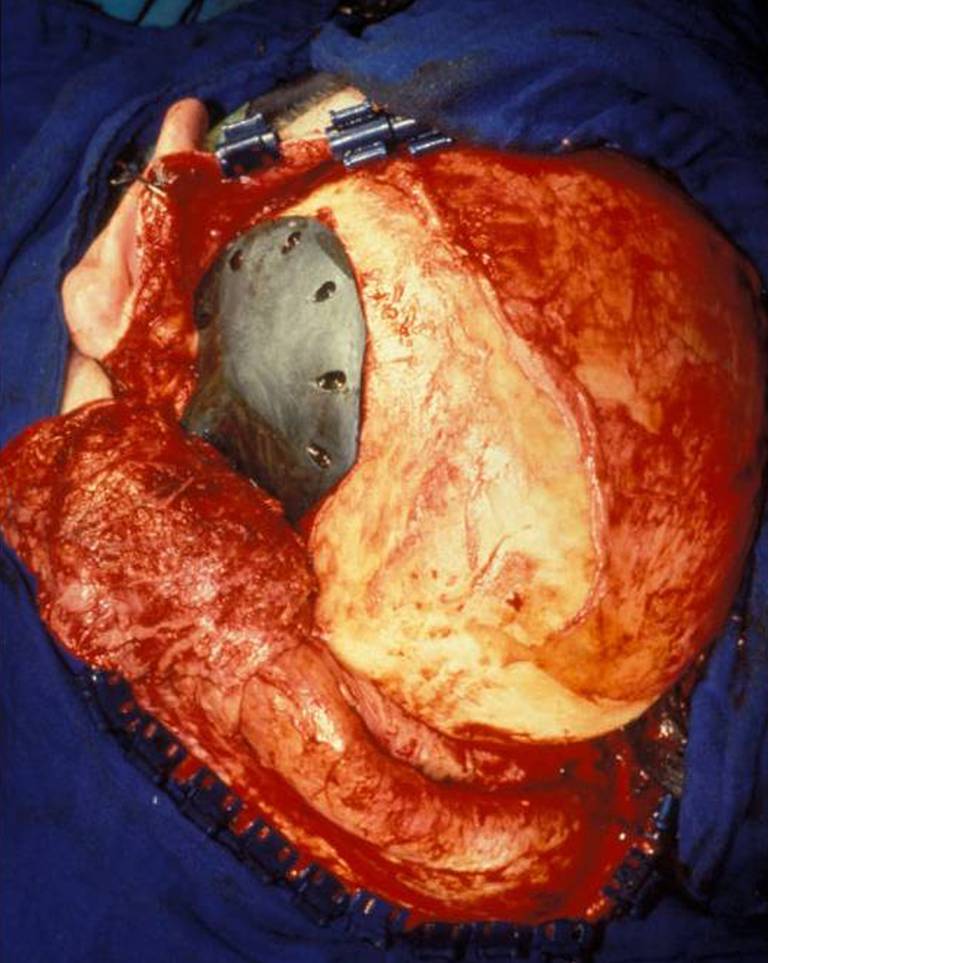

Bild vergrößern

Fig. 5

Intraoperative situs

Access to the site of defects was gained by employing the incision used in primary surgery, mostly a coronal incision. The periosteum was incised 1cm laterally to the defect, sheared off the bone at the rim of the defect and left in continuity with the dura mater. As the stereolithographic model used for building the implant is a model of the skull bone, the soft tissue has to be stripped off completely. If the temporal muscle was lifted, it was refixed to the periosteum of the undisturbed skull and to bore holes of the implant at the end of surgery (Fig. 6).

Dura reconstruction with periosteal flaps had to be performed two times. In two cases it was necessary to reduce intracranial pressure by application of mannitol in order to properly place the implant. In the cases of the primary reconstruction small details of the implant had to be recontoured with diamond fraises. Titanium screws applied through prefabricated holes were used to fix the implant. In places where the adjacent bone could not host a lag screw, miniplates were used.